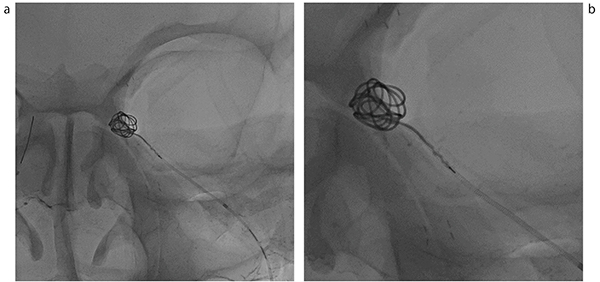

図3 超高精細検出器を用いた拡大撮影画像

a:FOV 3.3インチ

b:FOV 1.5インチ

頭部ファントム上のコイルの観察において,1.5インチまで拡大した場合でも劣化の少ない画像を得ることができる。